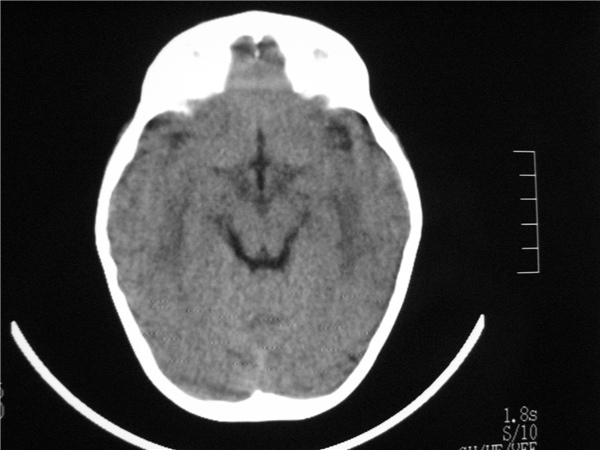

标题: PED2843: CT-23675 F 4Y 大家看看颅内有问题没。 [打印本页]

标题: PED2843: CT-23675 F 4Y 大家看看颅内有问题没。

四脑室扩大,三脑室稍扩大上移

胼胝体发育不全??

六脑室

四脑室扩大,,六脑室

四脑室扩大,密度降低,图像的问题?建议mr扫描。